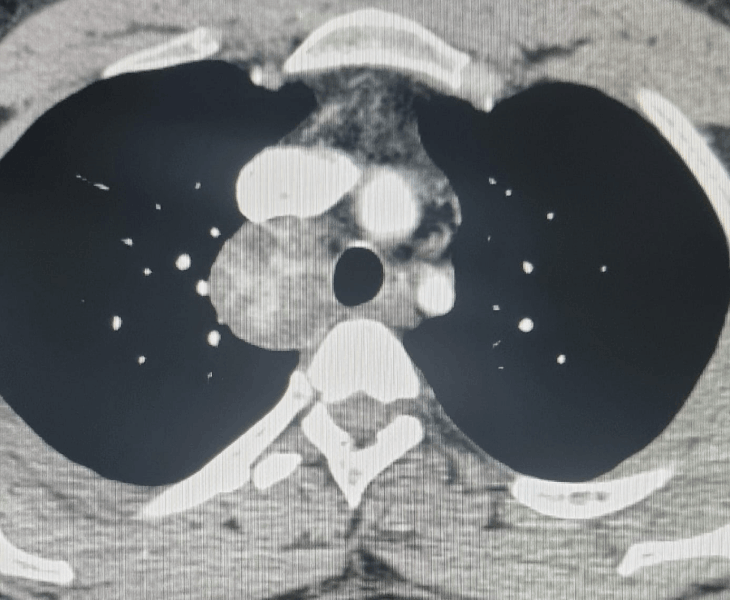

Lung & Mediastinal Biopsies

CT‑guided biopsies for suspected lung/mediastinal tumours and nodules.